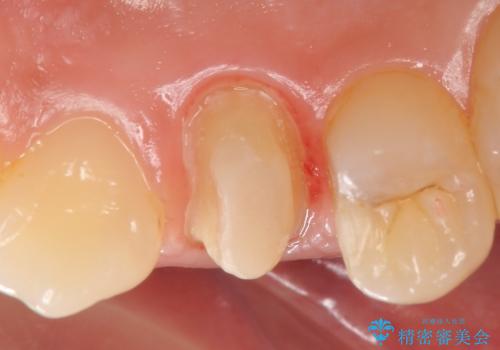

- 右上の歯茎の腫れが引かないので診て欲しいといらっしゃった方の症例です。

検査の結果、右上4番目の歯は神経が死んでおり、そのせいで歯茎に膿の出口が出来ていることがわかりました。

右上4は根管治療を行い、オールセラミッククラウンによる補綴を行いました。